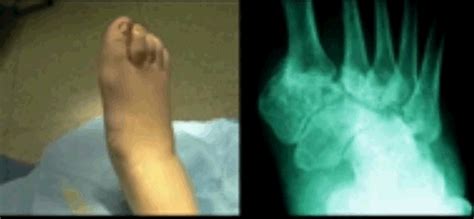

Charcot Foot : Charcot foot : May 01, 2018 · charcot neuroarthropathy of the foot and ankle is an inflammatory condition affecting the periarticular soft tissues and bone in persons with peripheral neuropathy, resulting in osseous.. Diabetic charcot neuropathy is a chronic and progressive disease that occurs as a result of loss of protective sensation which leads to the destruction of foot and ankle joints and surrounding bony structures. Now considered an inflammatory syndrome, the diabetic charcot foot is characterized by varying degrees of bone and joint disorganization secondary to. Charcot foot is a rare but serious complication that can affect persons with peripheral neuropathy, especially those with diabetes mellitus. For patient education resources, see the diabetes center , sexually transmitted diseases center , and foot, ankle, knee, and hip center , as well as diabetic foot care and syphilis. Feb 13, 2021 · charcot foot.

Charcot foot is a rare but serious complication that can affect persons with peripheral neuropathy, especially those with diabetes mellitus. However, it occurs most commonly in the lower extremity, at the foot and ankle. This condition causes the bones in the foot to become weak, making them prone to damage such as. The bones become weak and can break and the joints in the foot or ankle can dislocate. Feb 13, 2021 · charcot foot. First described in 1883, this enigmatic condition continues to challenge even the most experienced practitioners. Affected individuals may have foot abnormalities such as high arches , flat feet , or curled toes (hammer toes). Diabetic charcot neuropathy is a chronic and progressive disease that occurs as a result of loss of protective sensation which leads to the destruction of foot and ankle joints and surrounding bony structures. A charcot foot can develop as a serious complication of diabetes, where progressive destruction of the bones and joints of the foot leads to deformity, increasing the risk of developing diabetic ulcers and making it very painful and difficult to walk. They often have difficulty flexing the foot or walking on the heel of the foot. Charcot affects the bones, joints, and soft tissues of the foot or ankle. Take charge of your foot and ankle health with resources from footcaremd. Foot and ankle orthopaedic surgeons have the training and experience to keep your feet healthy and pain free.

Charcot affects the bones, joints, and soft tissues of the foot or ankle. A charcot foot can develop as a serious complication of diabetes, where progressive destruction of the bones and joints of the foot leads to deformity, increasing the risk of developing diabetic ulcers and making it very painful and difficult to walk. Affected individuals may have foot abnormalities such as high arches , flat feet , or curled toes (hammer toes). They often have difficulty flexing the foot or walking on the heel of the foot. Feb 13, 2021 · charcot foot. Charcot foot is a rare but serious complication that can affect persons with peripheral neuropathy, especially those with diabetes mellitus. May 01, 2018 · charcot neuroarthropathy of the foot and ankle is an inflammatory condition affecting the periarticular soft tissues and bone in persons with peripheral neuropathy, resulting in osseous. Foot and ankle orthopaedic surgeons have the training and experience to keep your feet healthy and pain free. Diabetic charcot neuropathy is a chronic and progressive disease that occurs as a result of loss of protective sensation which leads to the destruction of foot and ankle joints and surrounding bony structures. Now considered an inflammatory syndrome, the diabetic charcot foot is characterized by varying degrees of bone and joint disorganization secondary to. However, it occurs most commonly in the lower extremity, at the foot and ankle. First described in 1883, this enigmatic condition continues to challenge even the most experienced practitioners. This condition causes the bones in the foot to become weak, making them prone to damage such as.